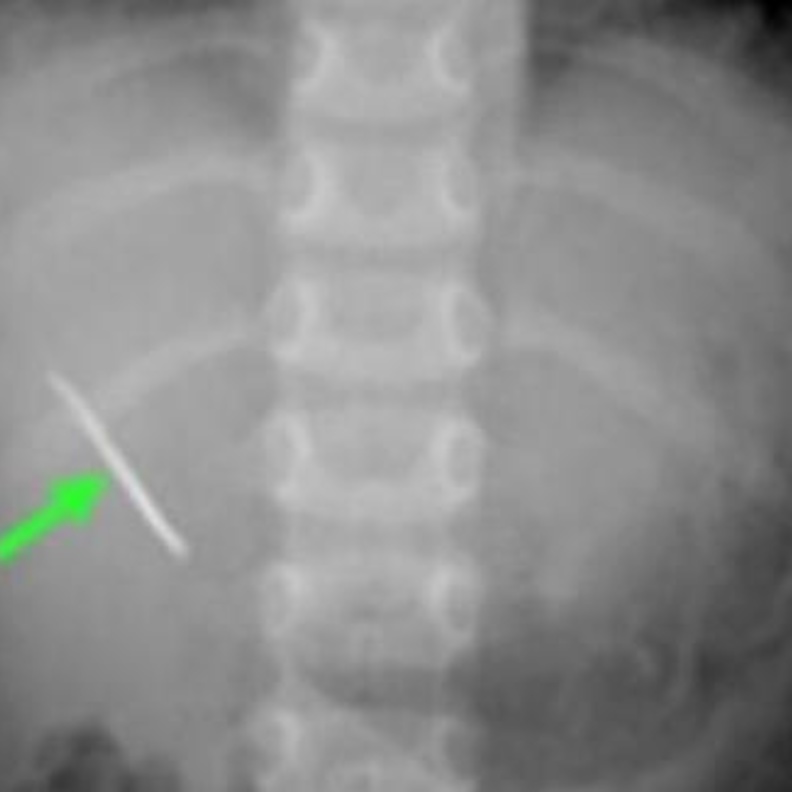

جراحة غريبة لطفل سعودي ابتلع دبوساً... فهل نجا؟

قصص واقعية